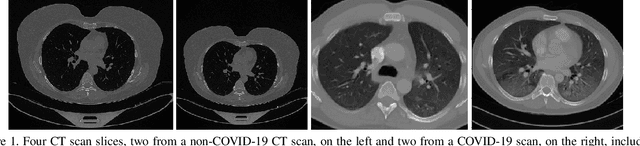

This paper presents the baseline approach for the organized 2nd Covid-19 Competition, occurring in the framework of the AIMIA Workshop in the European Conference on Computer Vision (ECCV 2022). It presents the COV19-CT-DB database which is annotated for COVID-19 detction, consisting of about 7,700 3-D CT scans. Part of the database consisting of Covid-19 cases is further annotated in terms of four Covid-19 severity conditions. We have split the database and the latter part of it in training, validation and test datasets. The former two datasets are used for training and validation of machine learning models, while the latter will be used for evaluation of the developed models. The baseline approach consists of a deep learning approach, based on a CNN-RNN network and report its performance on the COVID19-CT-DB database.